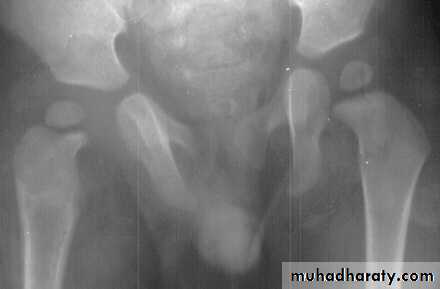

Imaging:

Ultrasonography: is a reliable method for revealing a joint effusion in early cases.X-ray: is normal early, then there will be widening of the radiographic ‘joint space’ and slight subluxation. Narrowing and irregularity of the joint space are late features.

MRI and CT: detection of early bone destruction and effusion.

Subluxation and dislocation of the joint (pathological).

Growth plate destruction and growth retardation.